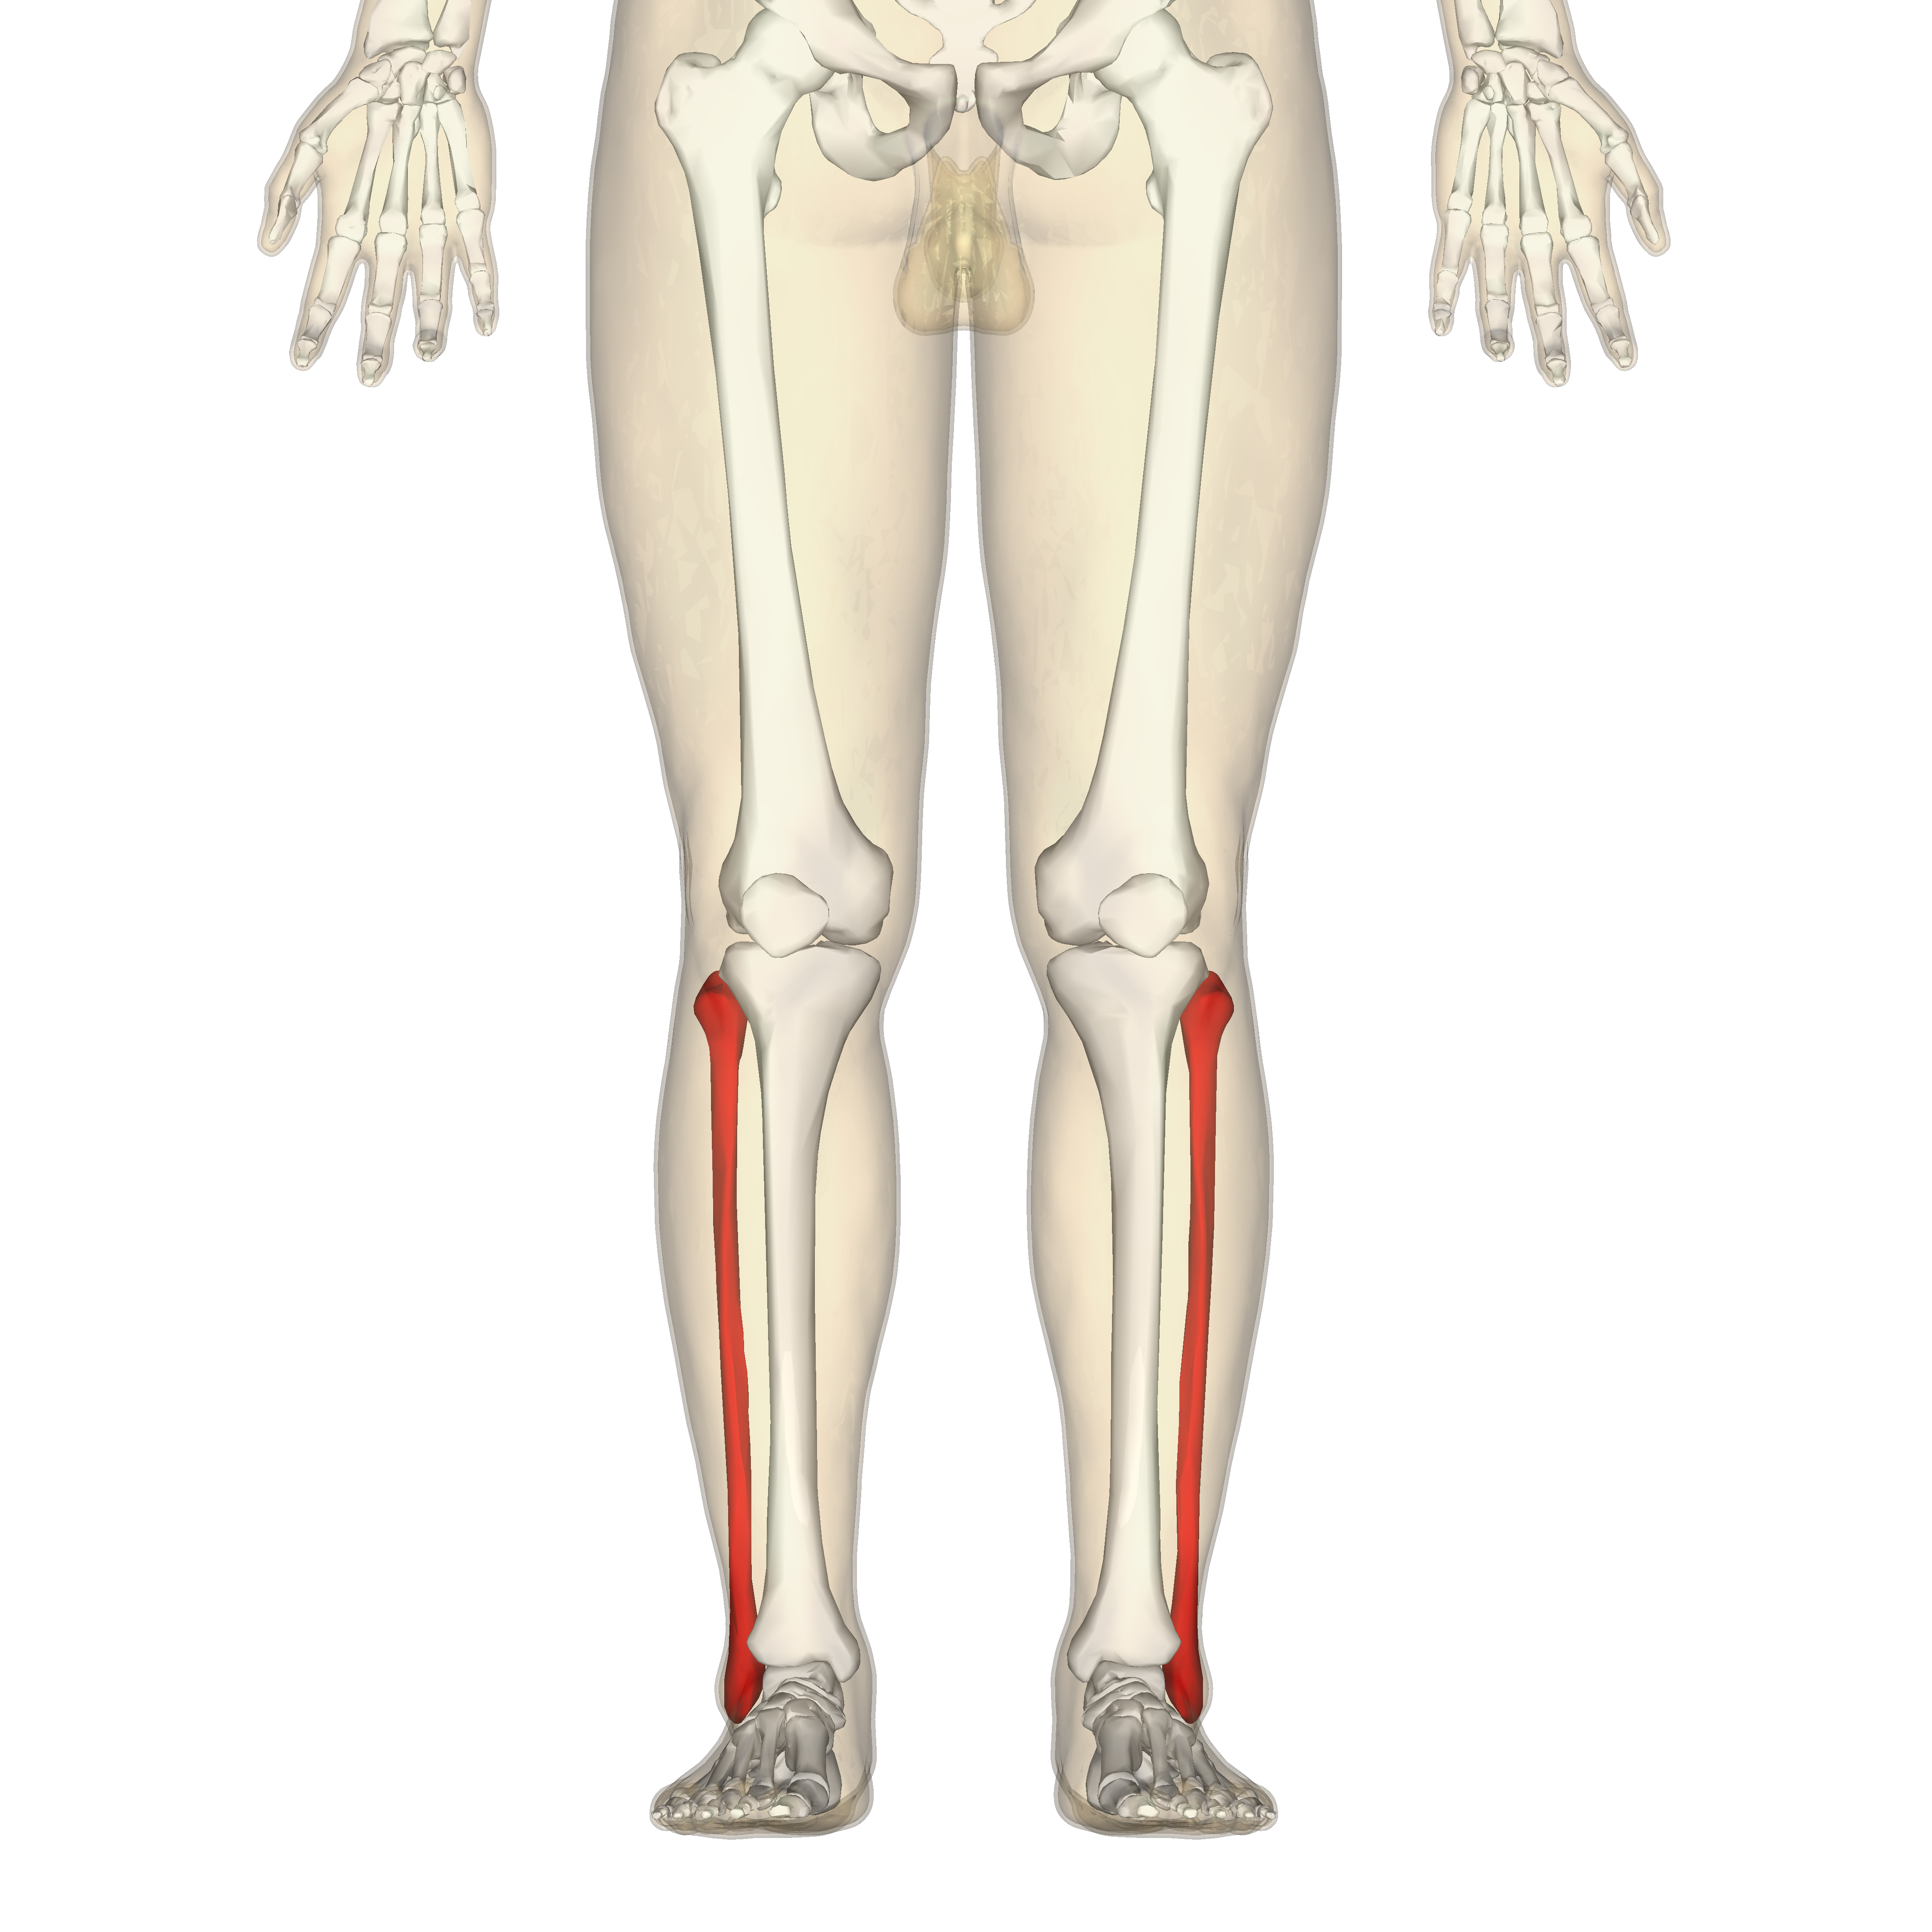

What is this region?

Fibula

Tibia